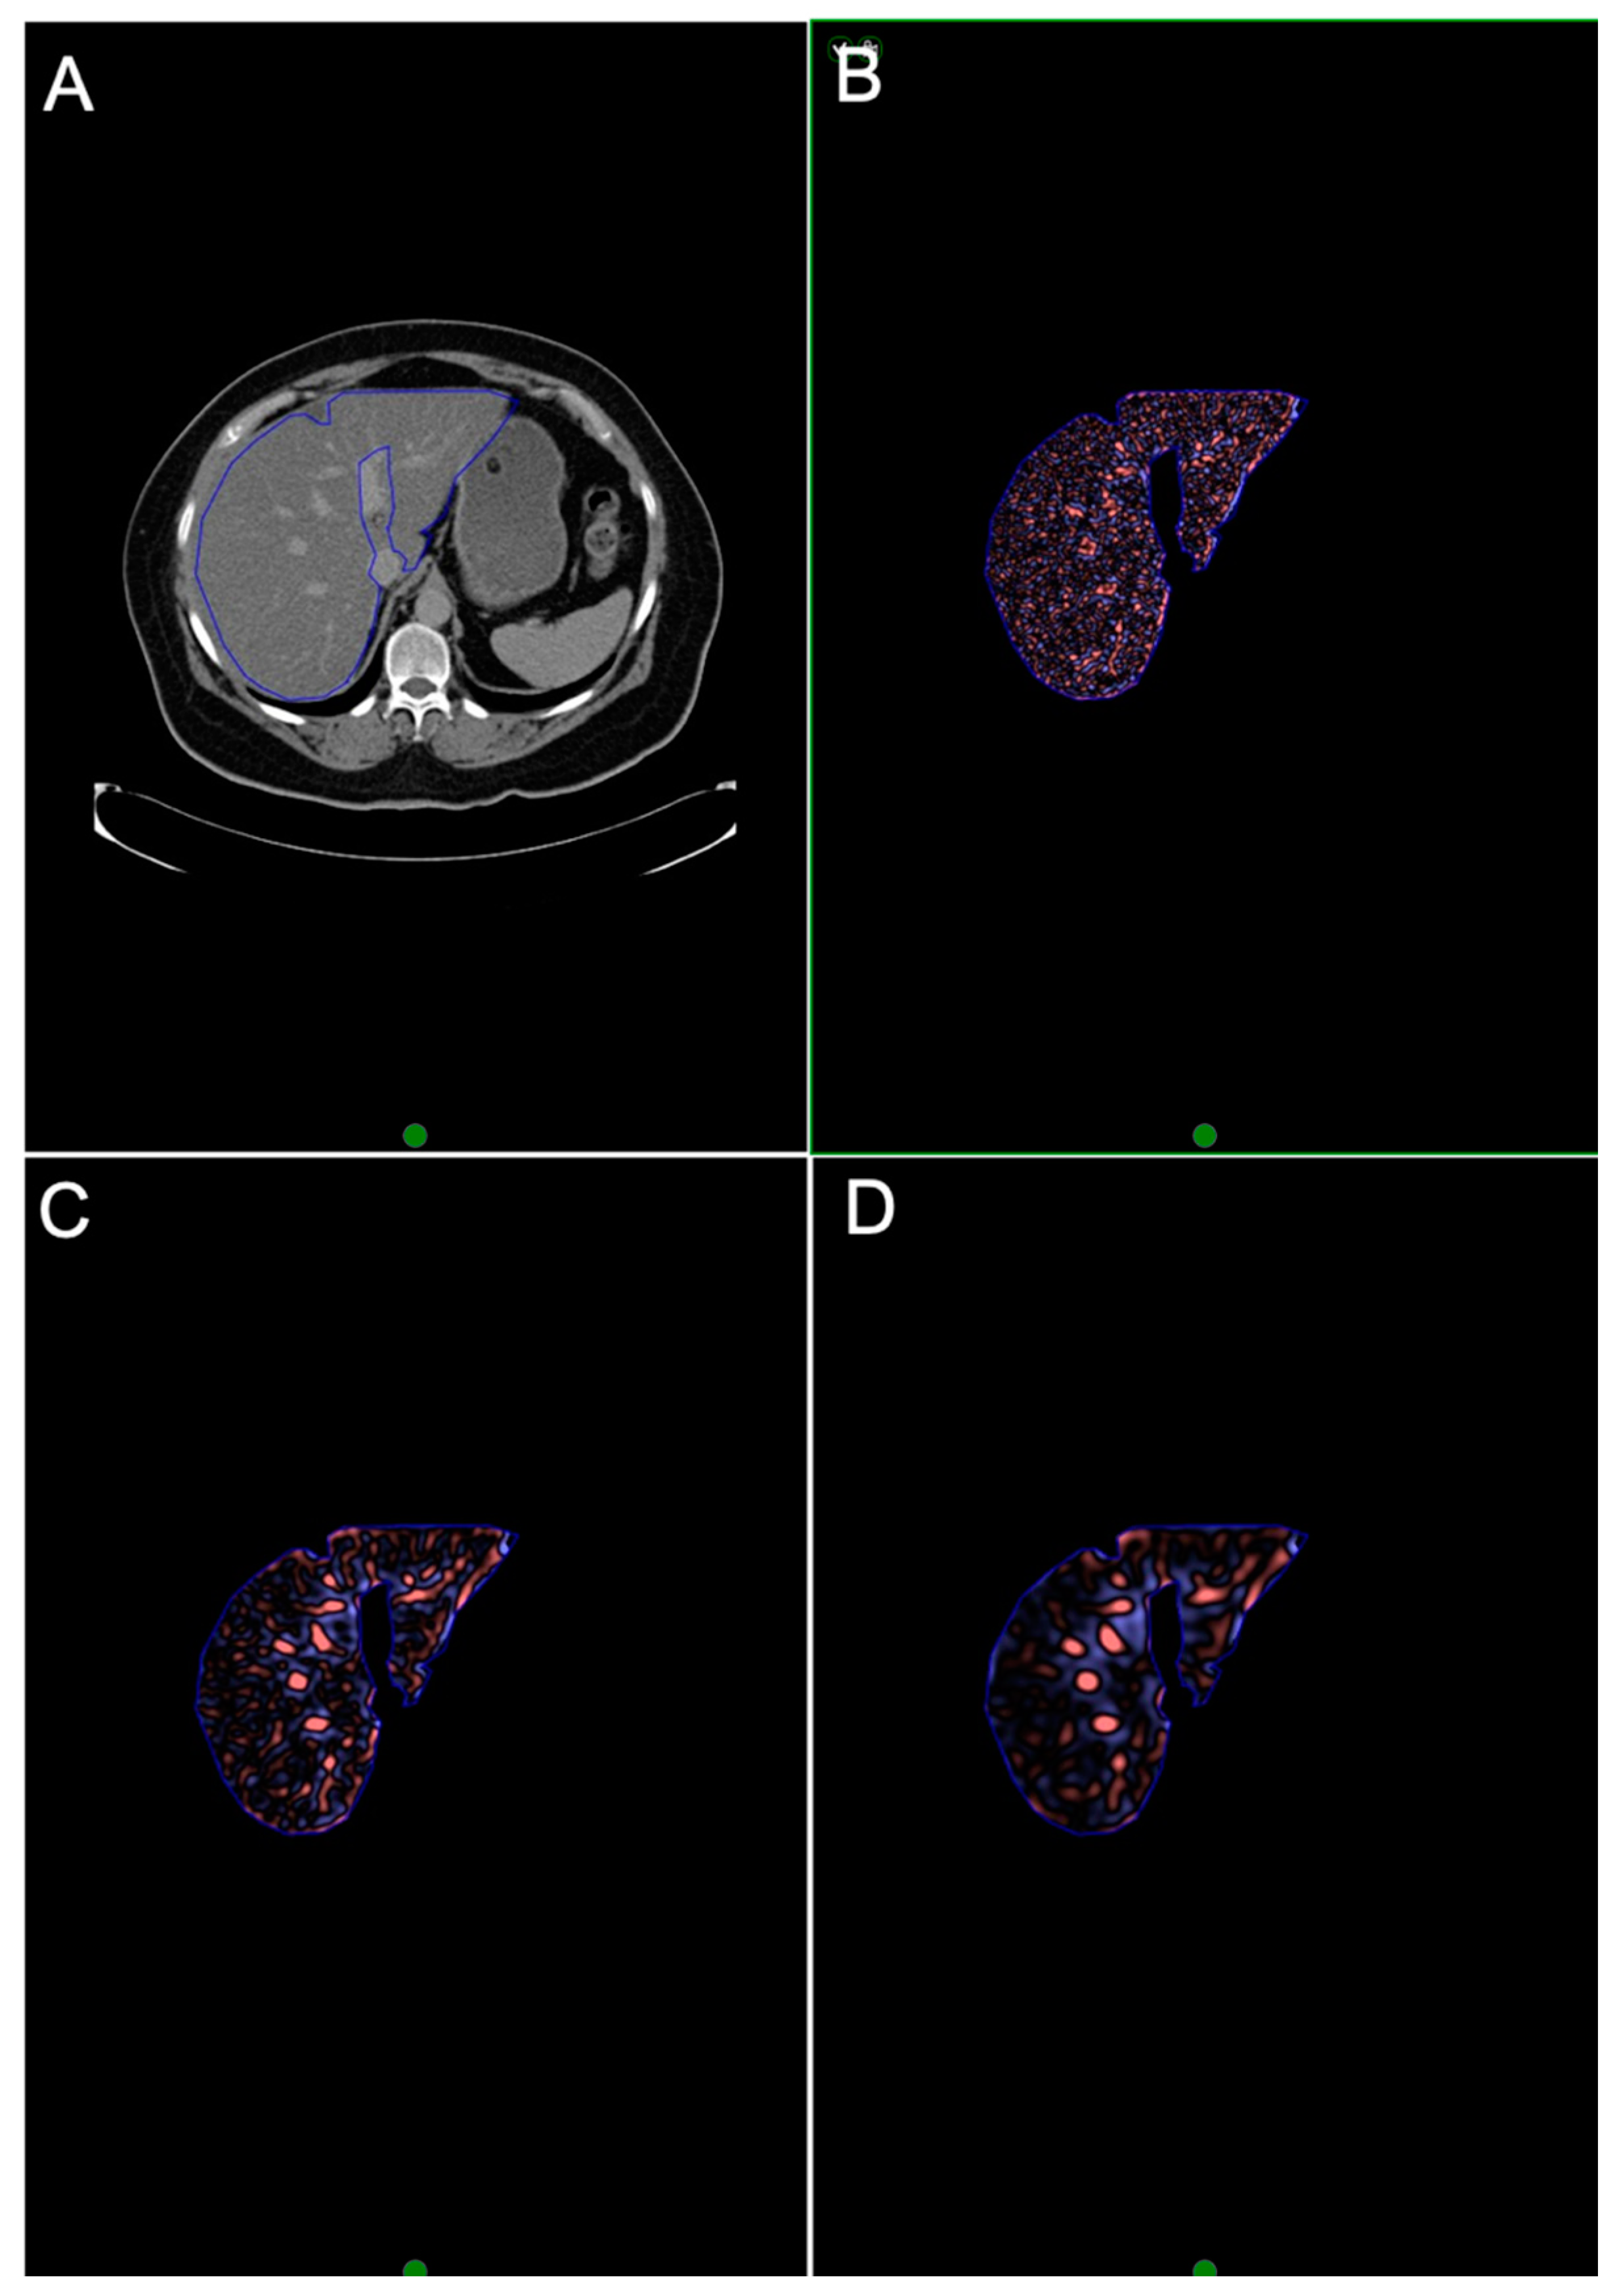

2.4. CTTA